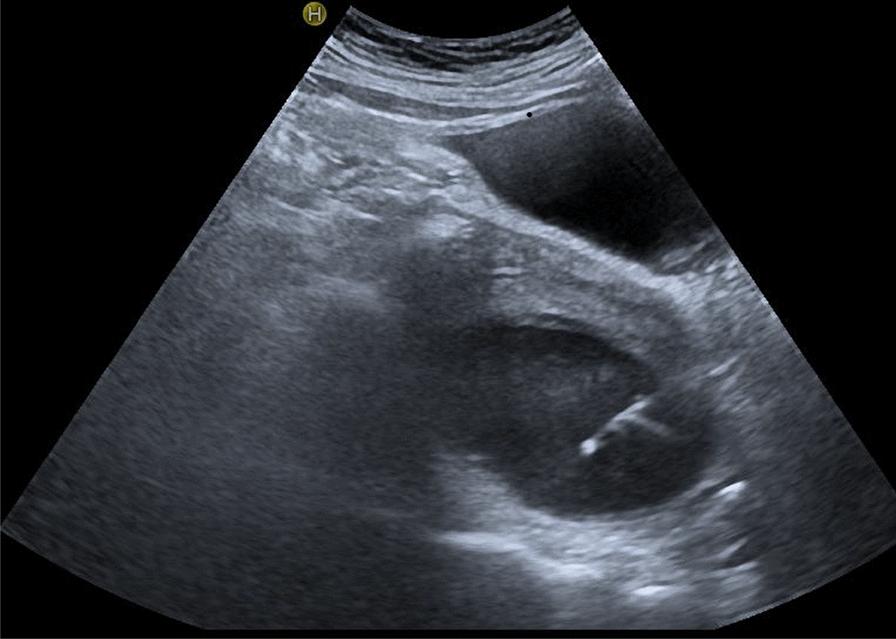

The management of postoperative fluid collections, which refers to the accumulation of fluid in the peritoneal cavity following pancreaticoduodenectomy, presents significant challenges. However, ultrasonography has emerged as a promising tool for diagnosing and guiding interventions for this condition. Ultrasonography offers several advantages, including accessibility, cost-effectiveness, and real-time imaging capabilities. It plays a crucial role in identifying ascitic fluid collections, characterizing their contents, and evaluating the severity of fluid collections. Moreover, ultrasound guidance enhances the safety and effectiveness of placing abdominal catheters. The aim of this study is to assess the diagnostic utility of ultrasonography in postoperative fluid collections following pancreaticoduodenectomy and evaluate the clinical efficacy of ultrasound-guided abdominal catheter placement.

Postoperative fluid collections is a commonly encountered concurrent condition following pancreaticoduodenectomy. Ultrasonography allows for the observation of diverse characteristics related to postoperative fluid collections, including its precise localization, sound transmission properties, and the presence of internal separations. Moreover, it enables timely guidance for precise placement of drainage tubes.